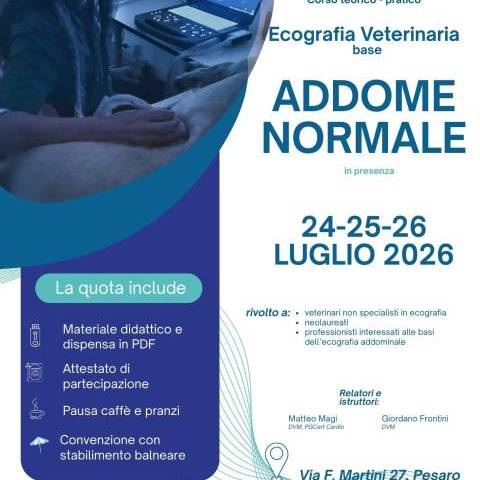

Informazioni Organizzative

Numero chiuso – massimo 15 partecipanti

Costo del corso

€ 400,00 iva incl.

Cosa Comprende la Quota

- Materiale didattico in formato digitale

- Coffee break

- Pranzi

- Convenzione con stabilimento balneare

- Attestato di partecipazione

Direttore del corso

Dr. Matteo Magi

DVM, Pg.Cert. Cardio.

Diagnostica ecografica

Fondatore e direttore scientifico di Ecopet

Sede del Corso

Pesaro – Via Martini 27 (PU)